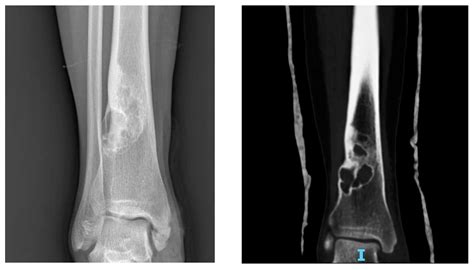

Bony lesions refer to any abnormal growths, defects, or changes in the bone tissue. These lesions can be benign (non-cancerous) or malignant (cancerous) and can occur in any part of the skeletal system. They are often detected through imaging techniques such as X-rays, CT scans, MRI, or bone scans. The characteristics of bony lesions can vary widely, making accurate diagnosis essential for appropriate treatment.

• Imaging Studies: X-rays, CT scans, MRI, and bone scans are commonly used to visualize the lesion and determine its characteristics.

• Biopsy: A tissue sample may be taken for histopathological examination to confirm the diagnosis and determine the type of lesion.